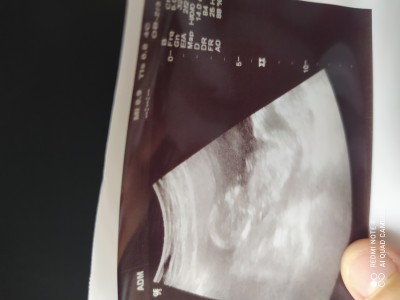

14 + 3 gittiginde kız gibi dedi net bişey soylemedi

Gebelik haftası 14+5

Çok net gözükmüyor resm

Kesin tahmin 16. Haftadan sonra söylüyorlar canım belki ondan söylememiştir